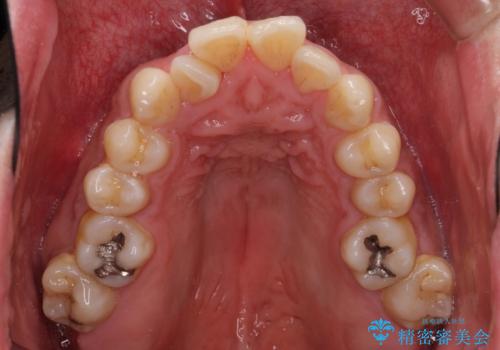

- 上下前歯のデコボコを気にして来院された患者様です。

デコボコは抜歯をすることなく解消できる程度であったため、インビザラインにより矯正治療を行うこととしました。

インビザラインは1日22時間を目標にマウスピースを装着することで歯列を改善するものです。

そのため、上下の歯が接触することはほとんどなく、マウスピースを介した咬合において歯列矯正が進んでいきます。